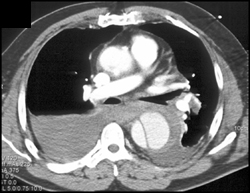

Clot in Innominate Vein